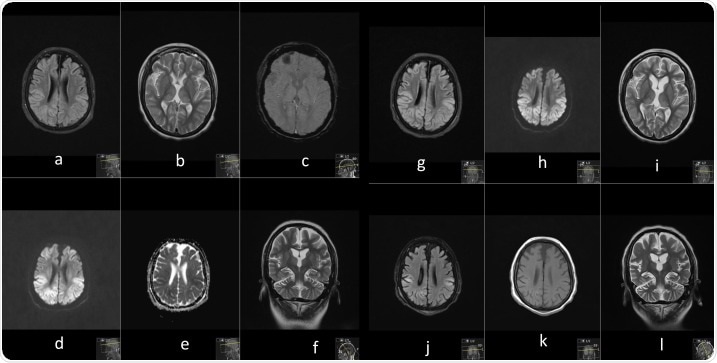

Serial contrast enhanced MRI brain performed prior to illness and at 3 time points during current illness. Image Credit: https://www.seizure-journal.com/article/S1059-1311(20)30362-9/fulltext

A time-dependent brain MRI - before illness, during illness, repeat, and follow-up - showed widespread bilateral cortical, cerebellar and thalamic signal change and swelling; persistent multifocal areas of neuroparenchymal signal change; and evolving laminar necrosis in the areas previously affected. Further episodes of suspected seizures persisted intermittently.